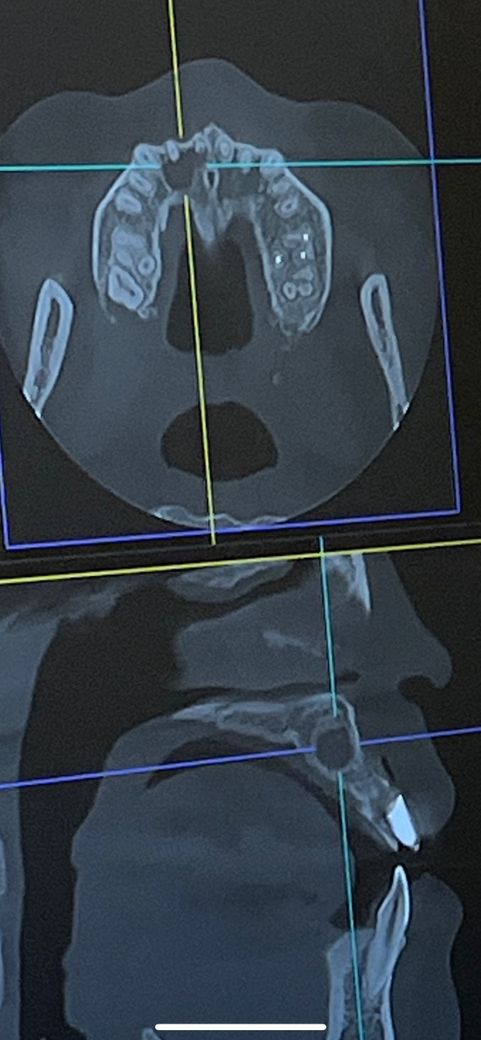

그런데 ct찍어보고는 대학병원 가야할 것 같다고 하네요…..

이렇게 엑스레이와 ct 로 볼때 결과가 차이가 날 수 있나요??

• 3번 째 사진

엑스레이는 단편적인 모습만 보는거고 CT의 경우에는 범위나 위치를 더 정확히 확인기 가능합니다.

염증이크고 주변 해부학적 구조를 건드릴 위험 때문에 대학병원의 전문과 처치를 권한것 같고요

일반엑스레이와 ct는 퀄리티 차이가 좀 날 수 있습니다